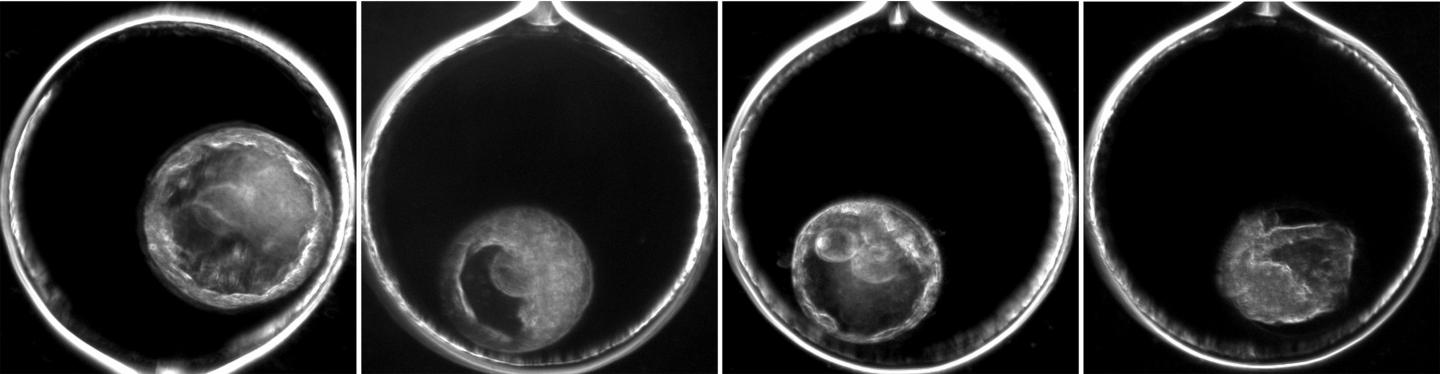

image: Researchers the Oregon National Primate Research Center at OHSU found that blastomeres (images 1-3) and their cellular fragments (image 4) can act as a trash bin within a mosaic embryo, and exclude genetic abnormalities.

Using advanced time-lapse imaging and single-cell sequencing techniques to precisely track the development of mosaic embryos of a rhesus macaque, Chavez and team identified a unique relationship between mosaicism and two other biological processes: cell fragmentation and blastomere exclusion.

In utero and after IVF, large cells formed by the division of a fertilized egg, known as blastomeres, may break down into small pieces called cellular fragments.

"We found that both the blastomeres and their fragments can act as trash bins within the embryo. As DNA-carrying cells divide and/or fragment, the embryo appears to naturally identify which blastomeres have genetic abnormalities and stop them from further development, " says Chavez, an assistant professor of reproductive and developmental sciences at ONPRC at OHSU, and an assistant professor of obstetrics and gynecology, and physiology and pharmacology in the OHSU School of Medicine. "By the stage that an embryo would implant into the uterus, these abnormal cells, or DNA have been visibly excluded from the rest of the embryo, suggesting that imperfect IVF embryos could be considered for use in transfer and might have the ability to endure in utero."